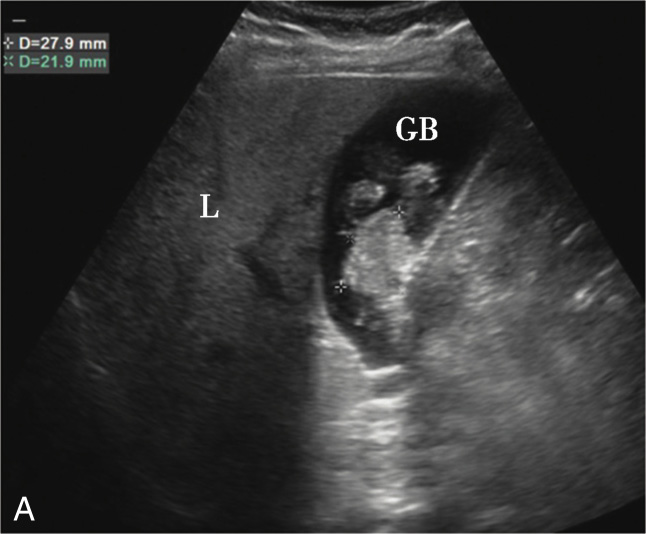

图2-5-2 厚壁型胆囊癌灰阶超声图像

A.胆囊颈部壁局限性增厚,回声不均(箭头所示)